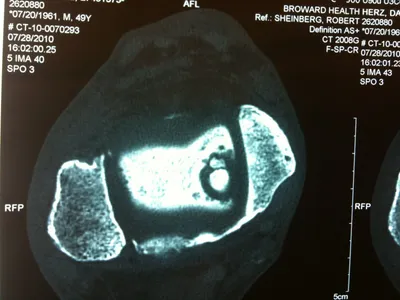

A series of intraop ankle arthroscopy pics of synovial chondromatosis with OCD talus and tibia and microfracture.

Pics of nodules removed during scope.  A separate incision had to be made to remove the nodules due to the size.